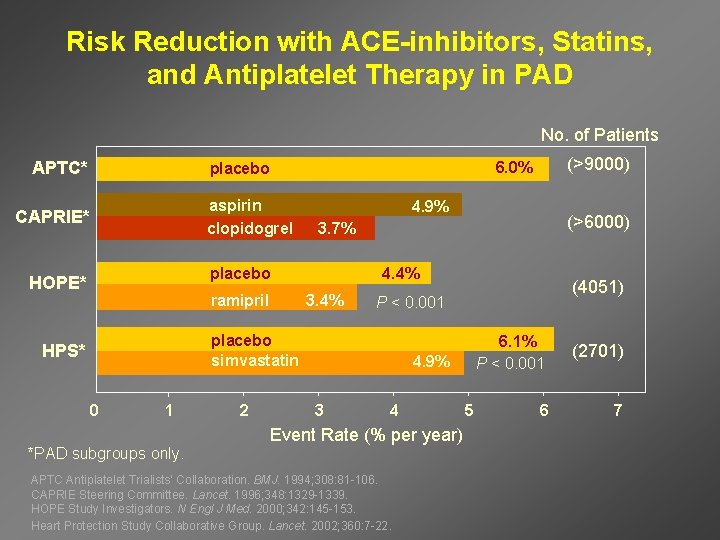

Risk Reduction with ACE-inhibitors, Statins, and Antiplatelet Therapy in PAD No. of Patients APTC* aspirin clopidogrel CAPRIE* 4. 9% ramipril 4. 4% 3. 4% 0 1 *PAD subgroups only. 2 (4051) P < 0. 001 placebo simvastatin HPS* (>6000) 3. 7% placebo HOPE* (>9000) 6. 0% placebo 4. 9% 3 4 Event Rate (% per year) APTC Antiplatelet Trialists’ Collaboration. BMJ. 1994; 308: 81 -106. CAPRIE Steering Committee. Lancet. 1996; 348: 1329 -1339. HOPE Study Investigators. N Engl J Med. 2000; 342: 145 -153. Heart Protection Study Collaborative Group. Lancet. 2002; 360: 7 -22. 5 6. 1% P < 0. 001 (2701) 6 7